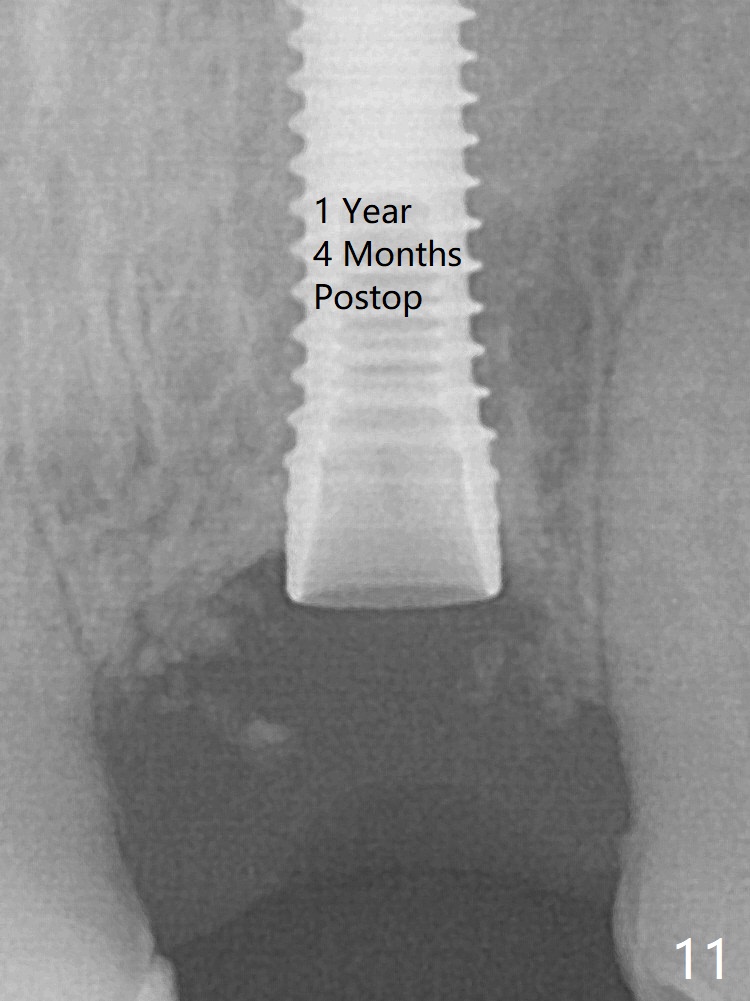

The mesial defect is filled with Vera Graft (Fig.7 *) and heals 1 year 4 months postop (Fig.11). The implant could be placed ~ 1 mm deeper (Fig.15).